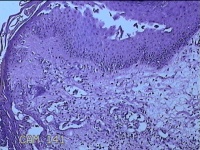

左侧会阴部结节

性别

女

年龄

43岁

临床诊断

皮肤良性肿瘤

一般病史

发现右侧会阴部结节3年余。

标本名称

大体所见

灰白粉红色带皮肤结节0.8x0.7x0.3cm一个,表面光滑,切开结节呈实性,切面灰白粉红色,质韧。